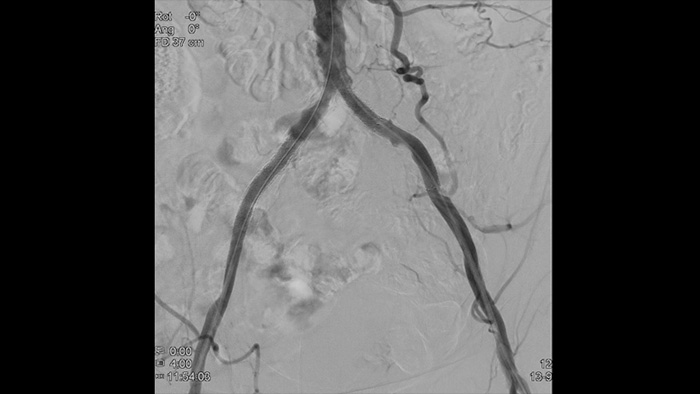

La solution Azurion de Philips a permis de percer dans l’amélioration des processus et ainsi d’obtenir des résultats prouvés en matière d’efficacité. Face au nombre croissant de patients atteints de maladies aortiques, Azurion offre un certain nombre d’innovations au niveau des processus de travail ayant pour but d’aider les équipes des services vasculaires à travailler de façon efficace et cohérente tout en restant focalisées exclusivement sur le patient et tout en gérant la dose de rayonnement pendant les interventions.

L’échographie intravasculaire est une technologie d’imagerie par cathéter qui permet aux médecins de visualiser les vaisseaux sanguins de l’intérieur pour faciliter l’évaluation de la présence et de l’étendue de la maladie. Elle facilite la prise de décision, le guidage et la confirmation du traitement interventionnel convenant à chaque patient.